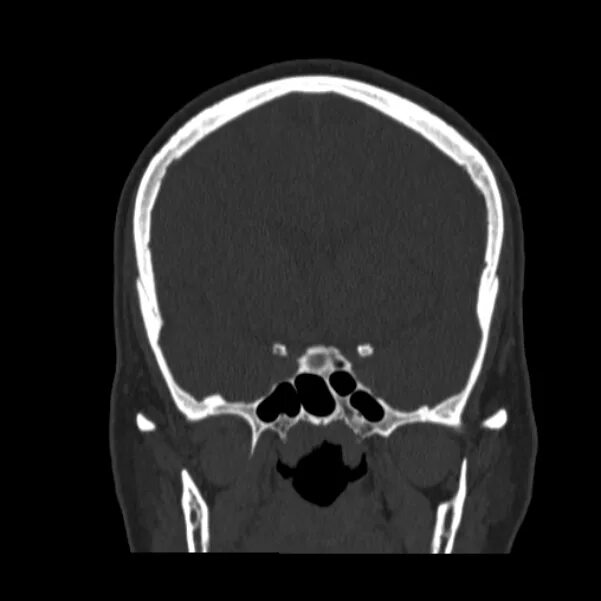

Череп на кт